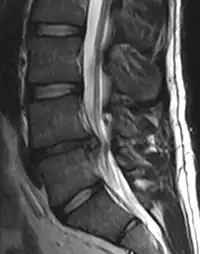

In most episodes, a specific underlying cause is not identified or even looked for, with the pain believed to be due to mechanical problems such as muscle or joint strain.[1][4] If the pain does not go away with conservative treatment or if it is accompanied by "red flags" such as unexplained weight loss, fever, or significant problems with feeling or movement, further testing may be needed to look for a serious underlying problem.[5] In most cases, imaging tools such as X-ray computed tomography are not useful and carry their own risks.[9][10] Despite this, the use of imaging in low back pain has increased.[11] Some low back pain is caused by damaged intervertebral discs, and the straight leg raise test is useful to identify this cause.[5] In those with chronic pain, the pain processing system may malfunction, causing large amounts of pain in response to non-serious events.[12]

An intervertebral disc has a gelatinous core surrounded by a fibrous ring.[34] When in its normal, uninjured state, most of the disc is not served by either the circulatory or nervous systems – blood and nerves only run to the outside of the disc.[34] Specialized cells that can survive without direct blood supply are in the inside of the disc.[34] Over time, the discs lose flexibility and the ability to absorb physical forces.[26] This decreased ability to handle physical forces increases stresses on other parts of the spine, causing the ligaments of the spine to thicken and bony growths to develop on the vertebrae.[26] As a result, there is less space through which the spinal cord and nerve roots may pass.[26] When a disc degenerates as a result of injury or disease, the makeup of a disc changes: blood vessels and nerves may grow into its interior and/or herniated disc material can push directly on a nerve root.[34] Any of these changes may result in back pain.[34]

Imaging is indicated when there are red flags, ongoing neurological symptoms that do not resolve, or ongoing or worsening pain.[5] In particular, early use of imaging (either MRI or CT) is recommended for suspected cancer, infection, or cauda equina syndrome.[5] MRI is slightly better than CT for identifying disc disease; the two technologies are equally useful for diagnosing spinal stenosis.[5] Only a few physical diagnostic tests are helpful.[5] The straight leg raise test is almost always positive in those with disc herniation.[5] Lumbar provocative discography may be useful to identify a specific disc causing pain in those with chronic high levels of low back pain.[43] Similarly, therapeutic procedures such as nerve blocks can be used to determine a specific source of pain.[5] Some evidence supports the use of facet joint injections, transforminal epidural injections and sacroilliac injections as diagnostic tests.[5] Most other physical tests, such as evaluating for scoliosis, muscle weakness or wasting, and impaired reflexes, are of little use.[5]